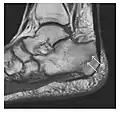

a

b

Figure 14: Subcapital insufficiency fracture in a 55-year-old man with a left hip pain without a history of trauma. Anteroposterior and Lauenstein view radiographs centered on the left hip do not show an obvious fracture line, but mild acetabular osteophytosis was noted consistent with hip osteoarthritis (not shown). (a) Coronal T1-weighted MRI shows a linear low-signal band through the femoral neck corresponding to a fracture line (arrowheads). (b) Bone scintigraphy shows focal uptake (arrow) corresponding to the fracture.[1]